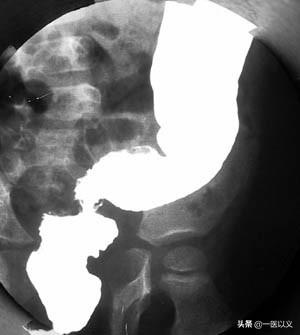

Alors que le lavement baryté joue un rôle important dans le diagnostic des patients atteints de colite ulcéreuse à un stade intermédiaire ou avancé.Un œdème et une ulcération de la muqueuse intestinale peuvent être détectés.

Critères diagnostiques de la colite ulcéreuse : ① exclure la dysenterie bacillaire, la colite amibienne, la schistosomiase, la tuberculose intestinale, la maladie de Crohn, l'entérite radique et d'autres causes d'inflammation du côlon ; ② avoir un tableau clinique typique et au moins une endoscopie ou une radiographie des changements caractéristiques de 1 ; ③ les symptômes cliniques ne sont pas typiques, mais il y a une coloscopie ou une radiographie typique ou une biopsie pathologique pour confirmer la colite ulcéreuse ; ③ les symptômes cliniques ne sont pas typiques, mais il y a une coloscopie ou une radiographie typique ou une biopsie pathologique pour confirmer la colite ulcéreuse.